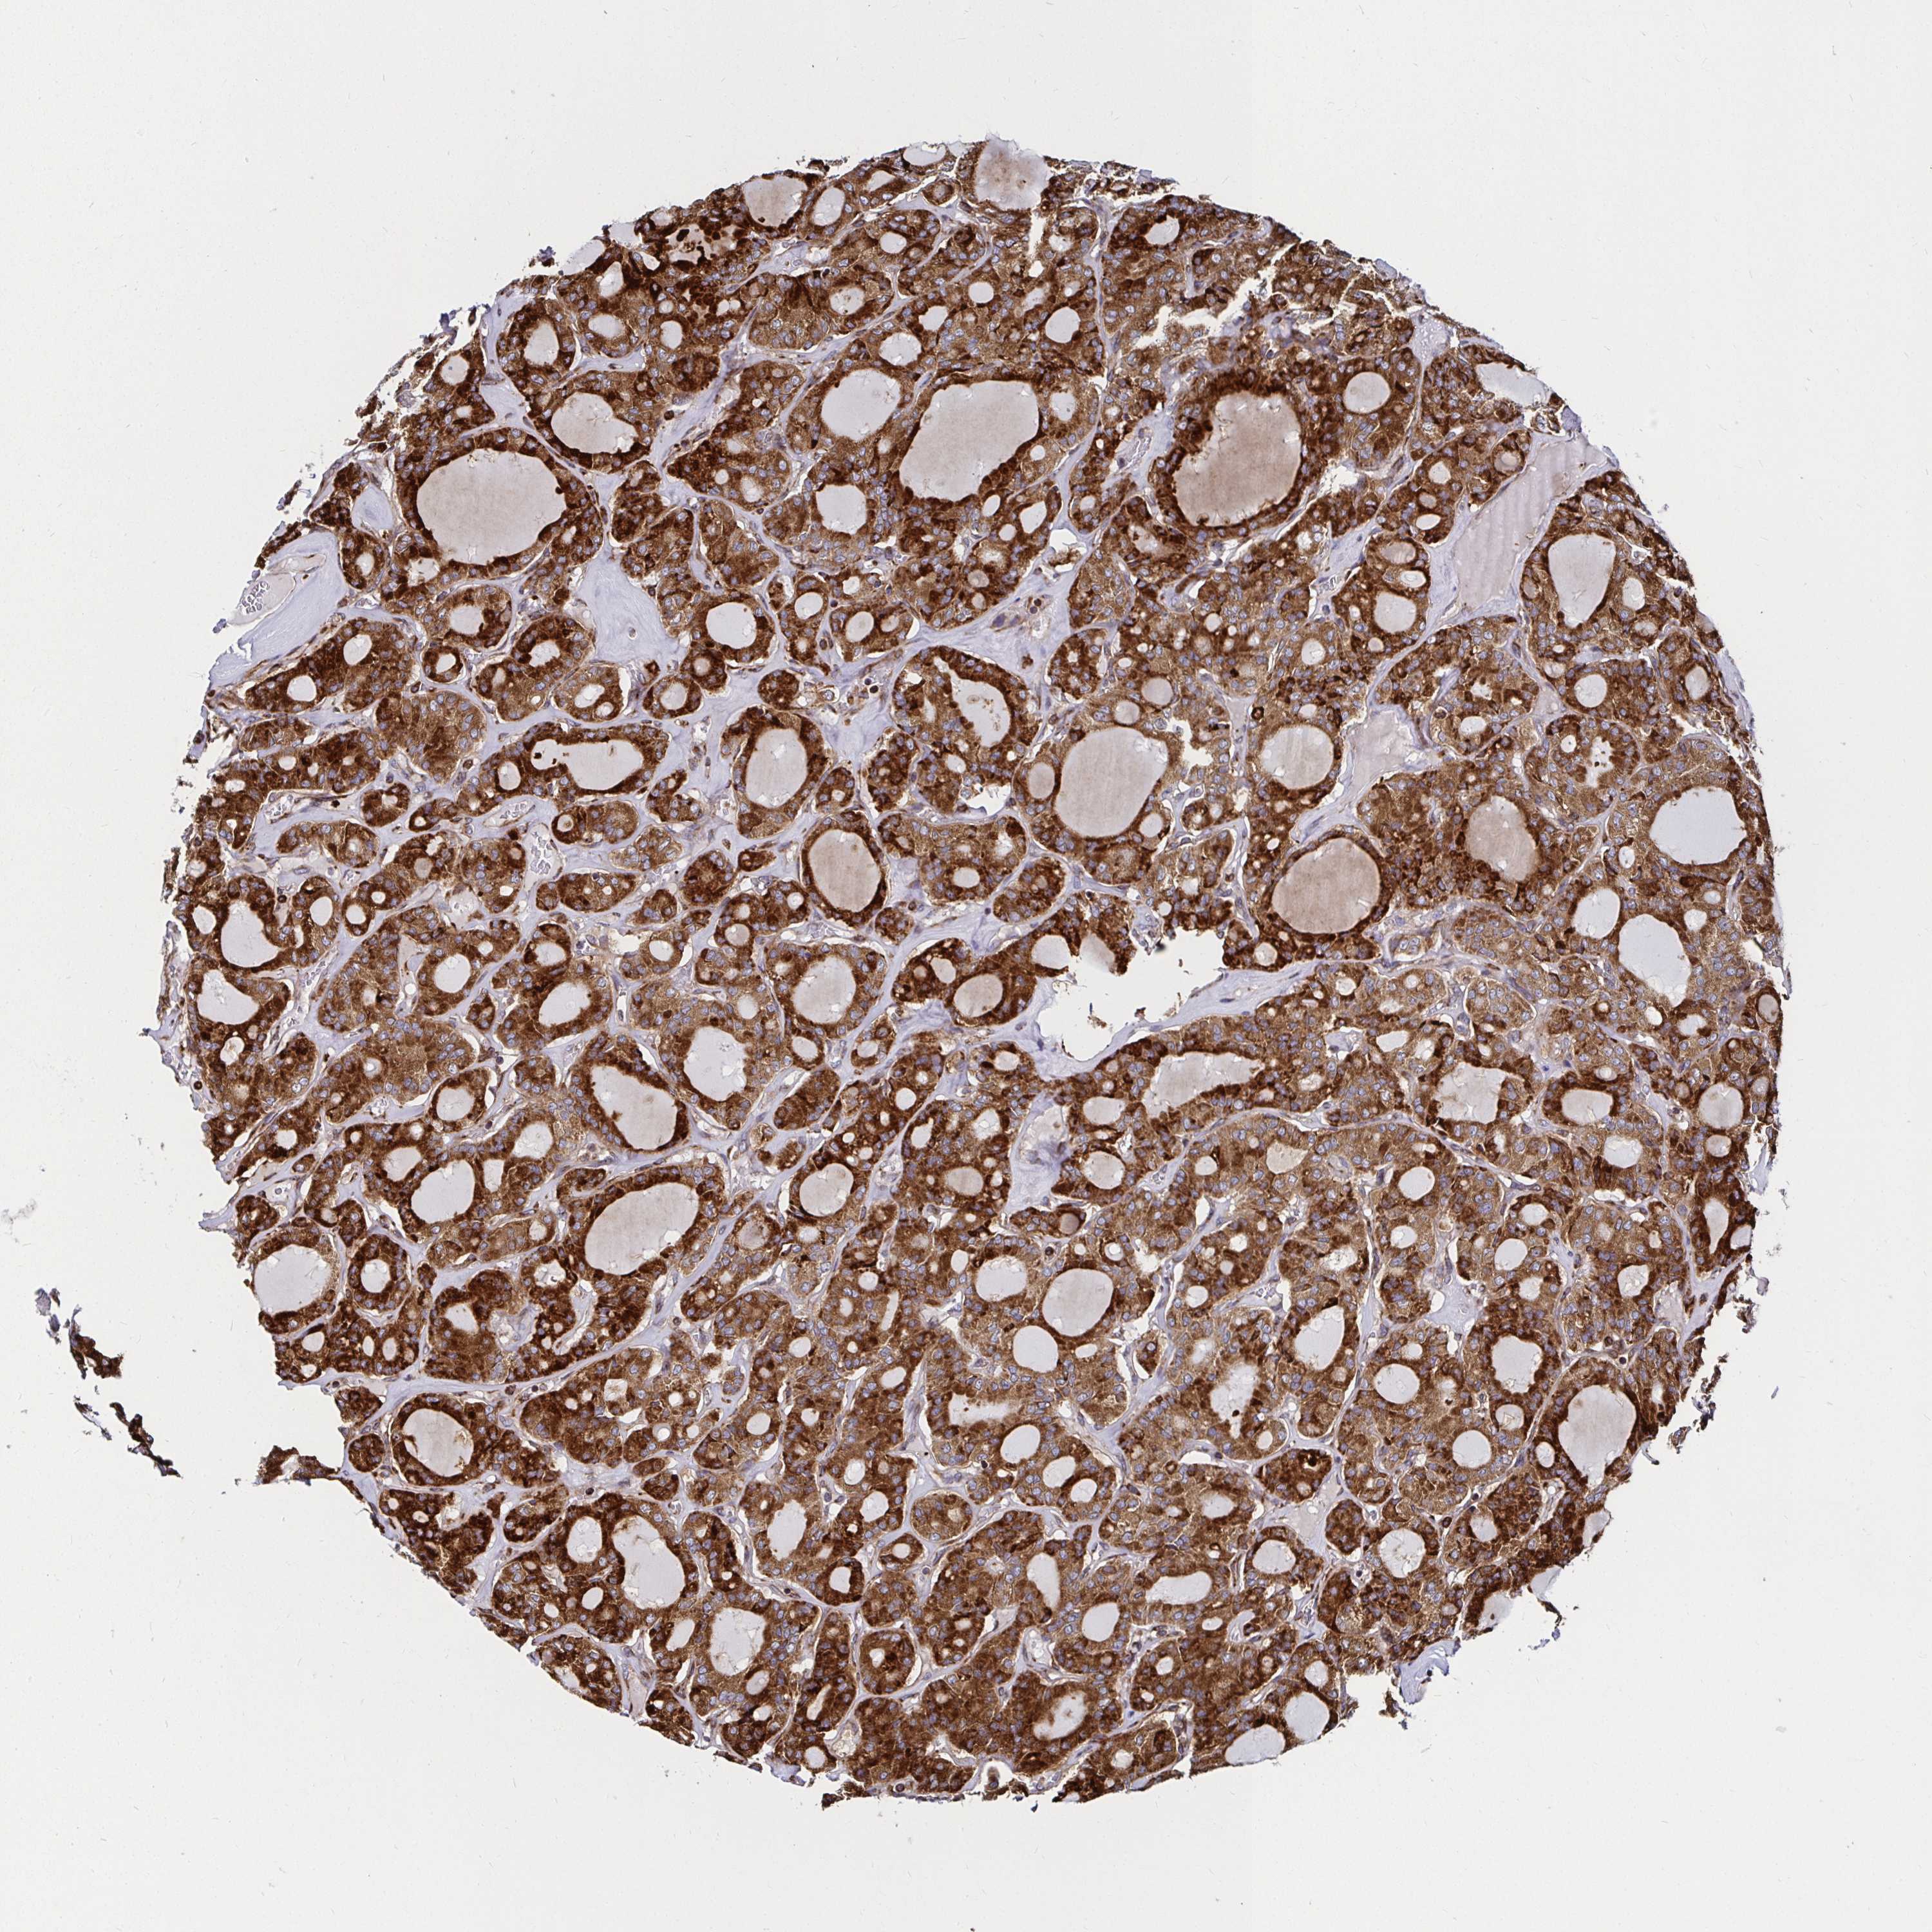

THYROID CANCER - Protein expressioni

A mouse-over function shows sample information and annotation data. Click on an image to view it in a full screen mode. Samples can be filtered based on level of antibody staining by selecting one or several of the following categories: high, medium, low and not detected. The assay and annotation is described here.

Note that samples used for immunohistochemistry by the Human Protein Atlas do not correspond to samples in the TCGA dataset.

Antibody stainingi

Antibody staining in the annotated cell types in the current human tissue is reported as not detected, low, medium, or high, based on conventional immunohistochemistry profiling in selected tissues. This score is based on the combination of the staining intensity and fraction of stained cells.

Each image is clickable and will lead to virtual microscopy that enables deeper exploration of all samples and also displays staining intensity scores, fraction scores and subcellular localization as well as patient and tissue information for each sample.

Antibody HPA045821

Antibody HPA054352

Antibody CAB012229

Staining

High

Medium

Low

Not detected

Intensity

Strong

Moderate

Weak

Negative

Quantity

>75%

75%-25%

<25%

None

Location

Nuclear

Cytoplasmic/membranous

Cytoplasmic/membranous,nuclear

Papillary adenocarcinoma, NOS

Follicular adenoma carcinoma, NOS